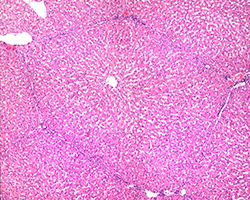

Órganos Linfoides

Órganos Linfoides

Ganglio linfático, bazo y timo.

(8 preparaciones) -